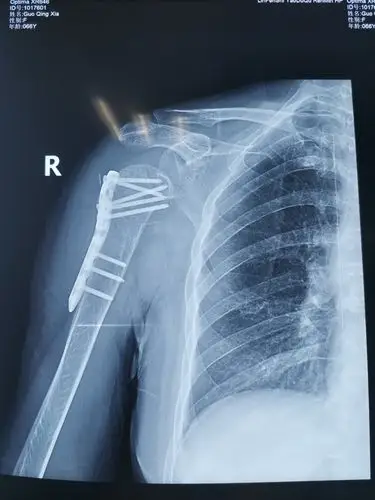

山西省首例反式肩关节置换术由向川主任团队成功开展 - 好大夫在线

术后右肩关节正位片